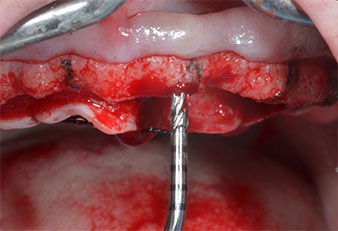

Поради сравнително твърдата кост (D2) в тази област, 10-милиметровото имплантно ложе в позиции 11 и 21 беше завършено с ротационен дрил с диаметър 4 mm в комбинация с W&H хирургичен обратен наконечник WS-75 L, W&H имплантологичен мотор Implantmed и опционалния W&H Osstell ISQ модул. За разлика от това, благодарение на меката кост, дисталните зони се подготвят до окончателен диаметър 3 mm, използвайки накрайник за Piezomed I3P. Имплантите най-накрая са поставени трансгингивално, за да остеоинтегрират за три месеца (Фиг. 6-10). Съществуващата протеза се фиксира на четирите временни импланта (Фиг. 8).